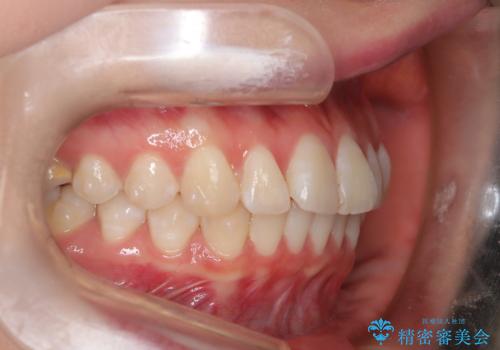

前歯のガタつきを治したい 翼状捻転マウスピース矯正

- 上顎前歯の突出、がたつき(翼状捻転)を主訴に来院されました。当院では総合歯科医療が可能であるため、矯正前処置として虫歯治療・歯周治療、親知らず抜歯を施行しました。その後、非抜歯かつ口元が出ないようなマウスピース治療を行いました。仕事柄、1日の装着時間が短くなってしまう時期もありましたが、患者様と相談しながら問題なく終了しています。